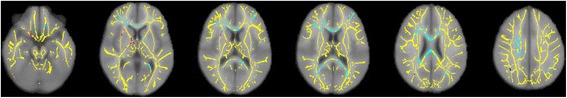

Results: In this study, 17 youth with OCD and 19 healthy control subjects, ages 10 to 19 years, underwent DTI on a 3T Siemens scanner. DSM-IV diagnoses were established with standardized interviews, and OCD symptom severity was evaluated using the Children's Yale-Brown Obsessive-Compulsive Scale (CY-BOCS). Voxel-wise analyses were conducted on data processed with tract-based spatial statistics (TBSS) to derive measures of fractional anisotropy (FA), axial diffusivity (AD), radial diffusivity (RD), and mean diffusivity (MD). OCD patients had significantly lower FA in seven WM clusters, with over 80% of significant voxels in bilateral frontal cortex and corpus callosum (CC). There were no regions of significantly higher FA in patients compared with controls. Patients also had significantly higher RD in right frontal cortex and right body of the CC. Earlier age at onset of OCD correlated significantly with lower FA in the right thalamus and with higher RD in the right CC. FA and RD were not significantly associated with symptom severity.

Conclusions: These findings point to compromised WM integrity and reduced myelination in some brain regions of children with OCD, particularly the CC and fiber tracts that connect the frontal lobes to widespread cortical and subcortical targets. They also suggest that age at onset may be a moderator of some of the WM changes in pediatric OCD.